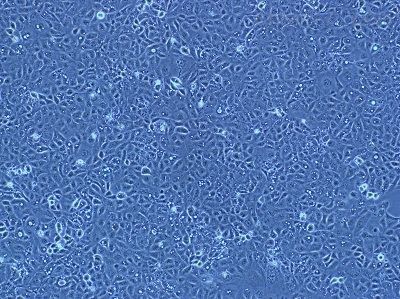

EFM-19(人乳腺癌细胞)复苏

人乳腺癌细胞